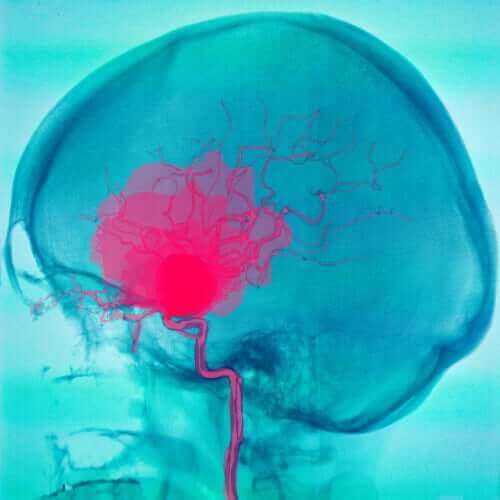

Beyin felci, beyinde meydana gelen bir hasar nedeniyle kişinin sakat kalmasına sebep olur. Bu hasar, kişinin hareket kabiliyetini ve duruşunu etkiler.

Beyin felci, bir kişinin hareketini, dengesini ve duruşunu etkileyen bir dizi bozukluğu ifade eder. Doğumdan sonra, ilk birkaç yıl içinde ortaya çıkabilir. Çoğu zaman bu bozukluğa neden olan yaralanma hamilelik sırasında meydana gelir.